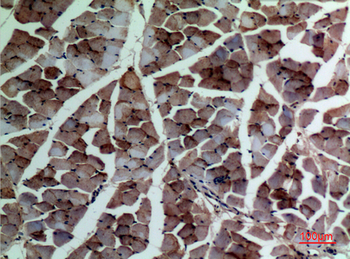

α-SMA Polyclonal Antibody

Catalog Number: orb1411650

| Catalog Number | orb1411650 |

|---|---|

| Category | Antibodies |

| Description | Rabbit polyclonal antibody to α-SMA. |

| Clonality | Polyclonal |

| Species/Host | Rabbit |

| Conjugation | Unconjugated |

| Reactivity | Human, Mouse, Rat |

| UniProt ID | P68133 |

| Tested applications | IHC-P, WB |

| Dilution range | WB: Western Blot: 1/500 - 1/2000. IHC-p: 1:100-300 ELISA: 1/20000. Not yet tested in other applications. |

| Storage | Maintain refrigerated at 2-8°C for up to 2 weeks. For long term storage store at -20°C in small aliquots to prevent freeze-thaw cycles |

| Alternative names | ACTA1; ACTA; Actin, alpha skeletal muscle; Alpha-a Read more... |

| Note | For research use only |